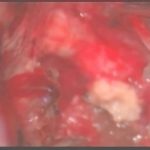

摘出 前

摘出 中

摘出 後